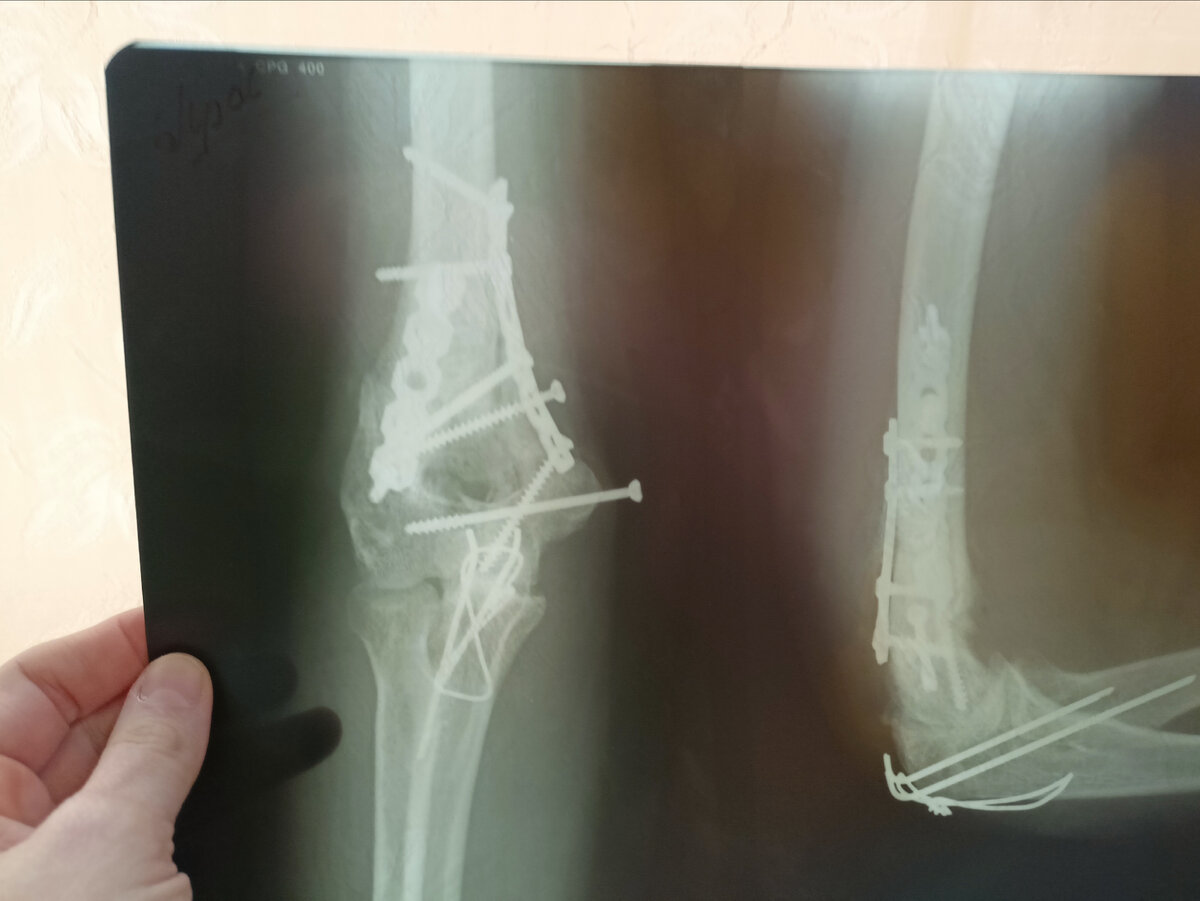

Рука киборга. Шурупы, пластины, спицы и проволока